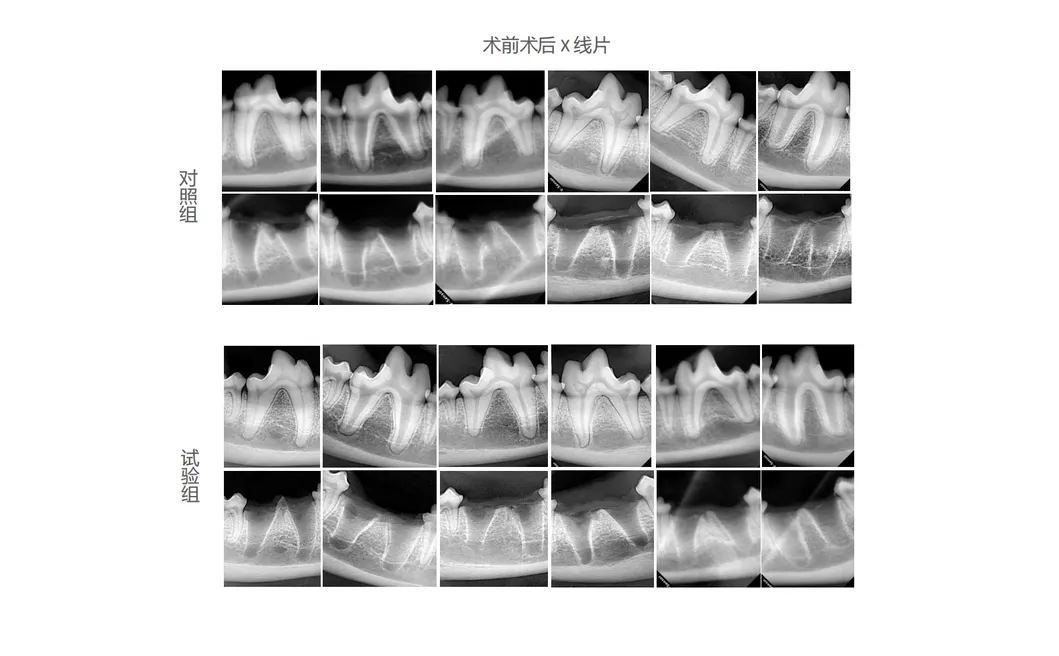

In this scientific study, canine subjects were selected to evaluate the effectiveness of the Golden Cudgel-Pneumatic Dental Elevator Kit compared to traditional manual devices. Researchers documented physiological parameters, intraoperative complications, extraction duration, and socket damage.